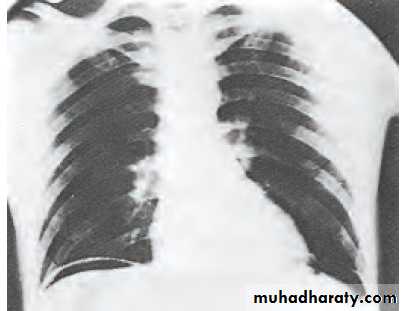

An erect plain chest radiograph will reveal free gas under the diaphragm in excess of 50% of cases with perforated peptic ulcer but CT imaging is more accurate . All patients should have serum amylase performed, as distinguishing between peptic ulcer, perforation and pancreatitis can be difficult.